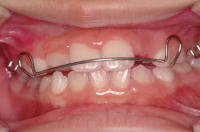

デーモンシステム 症例

![]() 治療前 |

![]() 矯正治療 |

![]() 治療後 |

「痛みが少なく治療期間が(従来のブラケットに比べると格段に)短い」

この症例はなんと非抜歯で8ヶ月で終了してしまいました

(副院長が担当ですがとても上手です)。通常ならば2~3年はかかると思います。